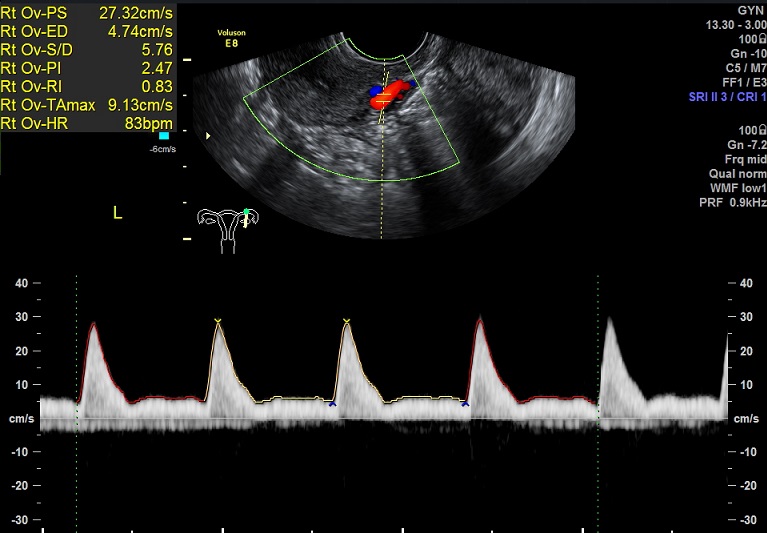

2015-3-19 月经第24天检查 内膜厚0.6cm 内膜血流:1级 内膜波动不明显 左卵巢黄体 子宫动脉: L:PSV:27.3cm/s EDV:4.7cm/s RI:0.83 S/D:5.8 PI:2.5 R: PSV:28.8cm/s EDV:2.0cm/s RI:0.93 S/D:14.4 PI:3.8 舒张早期血流缺失 检验: 2015-3-11 E2: 155.42 LH: 7.00 FSH: 4.43 P: 2.45 |

2015-3-19图示